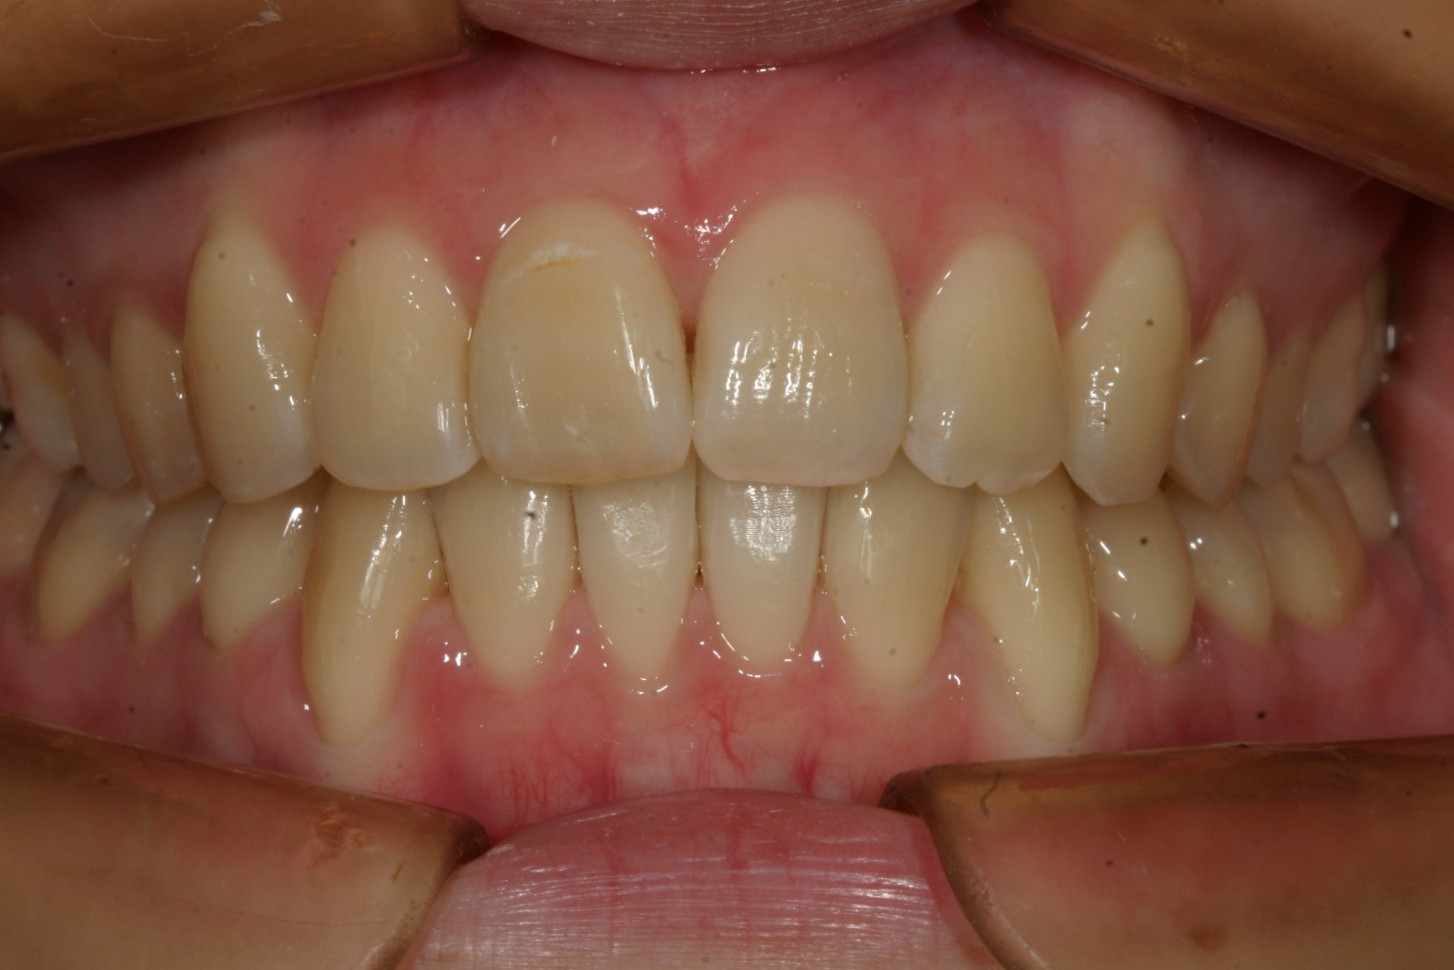

短期間で綺麗に改善しました。

出っ歯もこんなに改善です。

こちらの症例は典型的な症例で歯列形が悪い為の不正咬合です。

これって言って特別何をしたって事無く歯列を V字形をU字形にするだけでここまで改善します。